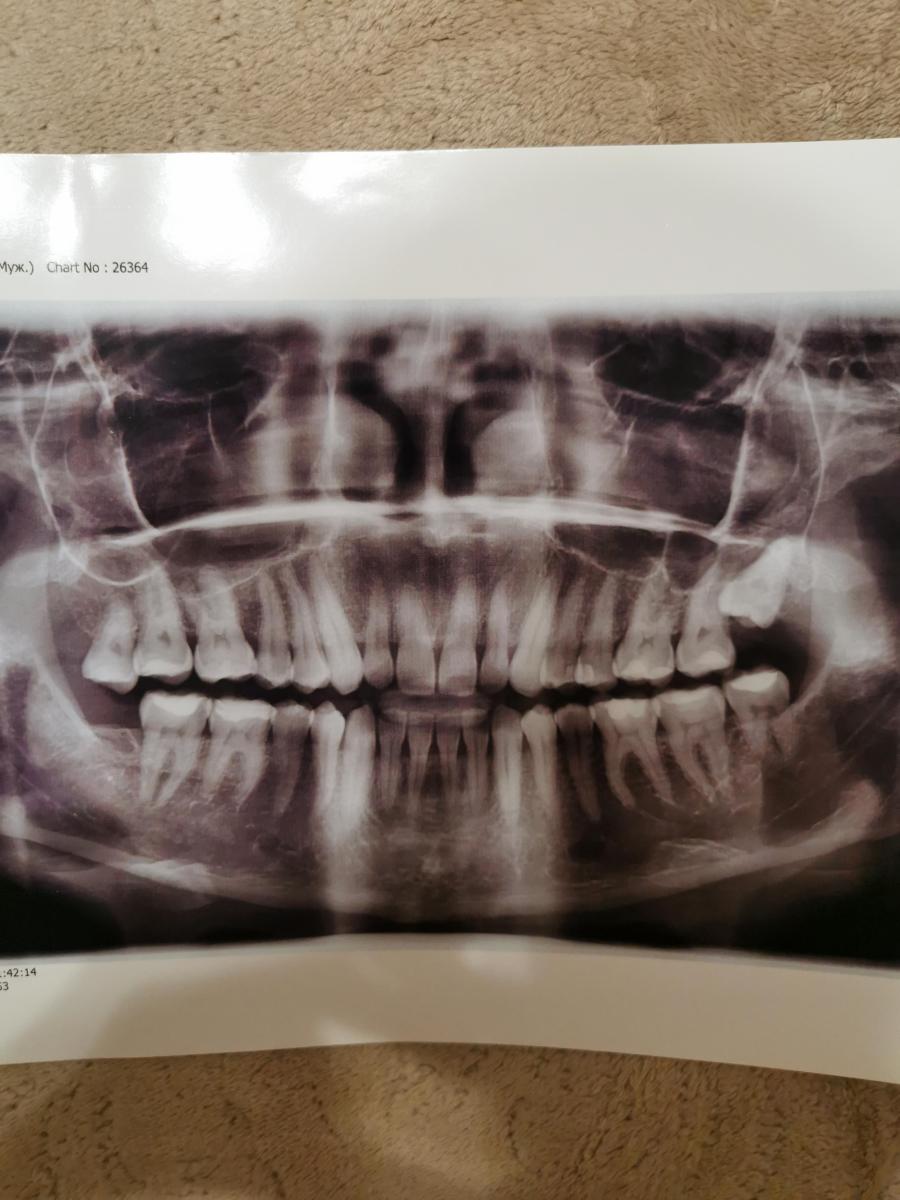

Добрый день! В 22 году ходил к стоматологу и ортодонту, сделали снимки, лечили зубы и сказали нужно удалять зуб мудрости. Все это было в платной клинике, удалить зуб решил в бесплатной, но ни в одной из 3-х бесплатных клиник не удалили, сказали нет необходимости). Больше не ходил и забил на это дело, сегодня разбирал документы и попался снимок 22 года и вот хочу у вас поинтересоваться нужно все таки удалять или нет?)

Upd: план лечения в 22 году.